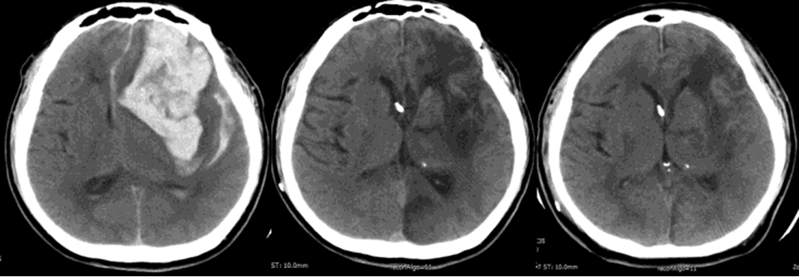

一位 51 岁男性患者,因左额顶叶脑出血性卒中陷入植物状态,伴有高血压病史,出院时需气管切开和鼻胃管喂养,家庭护理期间毫无改善。

随后他接受了脑室间充质干细胞移植:3 周后首次移植,1 个月、2 个月时再次移植,全程无不良反应。随访结果令人惊喜:3 个月、6 个月、12 个月时,他的 NIHSS(国家卫生研究所卒中量表)评分从 23 分分别降至 20 分、19 分、19 分;12 个月时,他已能坐在轮椅上,成功脱离气管切开管和鼻胃管,影像学还显示枕部梗死面积和血肿周围低密度区域明显缩小。